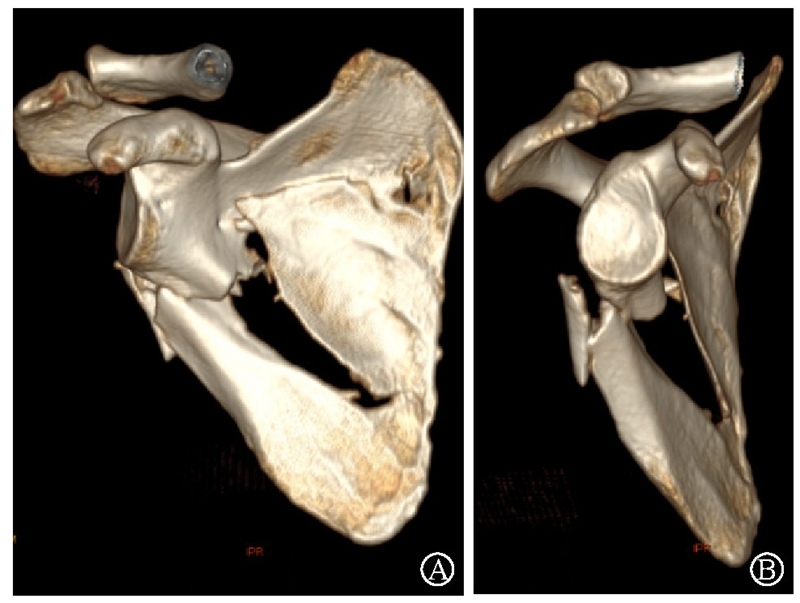

术中采用钢板固定肩胛颈内下方骨折块,肩胛骨体部骨折固定采用缝线辅助固定技术,骨折端以Nice结固定。术后CT三维重建显示骨折复位满意,固定良好(图22)。

图22 术后CT三维重建示肩胛骨骨折复位满意,内固定位置良好 图A:肩胛骨后面观;图B:肩胛骨侧面观

病例4为53岁男性患者,因高处坠落导致右肩胛骨骨折,合并右侧第3、5、7、8肋骨骨折(图20-21)。

图21 术前CT三维重建示肩胛颈及肩胛骨体部骨折 图A:肩胛骨前面观;图B:肩胛骨侧面观